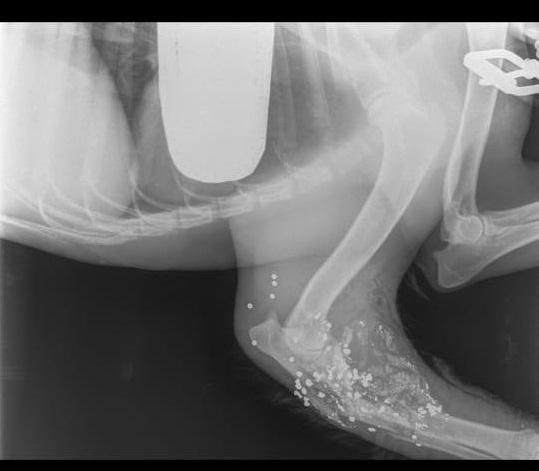

Собак увозят в клинику. Теперь обе без лап — у девочки ампутирована часть лапы, у мальчика полностью.

В клинике из лап собак достали дробь. Участковому предложили её забрать и приобщить к делу. Фиг там — участковый заявляет, что ему не нужна эта улика. Ему на всё насрать или у него что-то с сознанием?